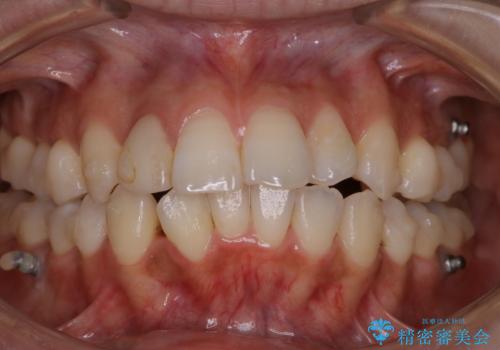

表のワイヤー矯正治療中にPMTCで綺麗に